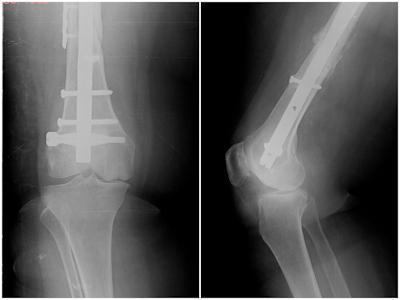

A partial knee replacement is suitable for patients with joint degeneration confined to a single compartment of the knee. The patient should preferably be older than 60 years of age, however unicondylar knee replacement can safely be performed in patients in their fifties if other treatment alternatives have failed. The pain should be localized to the involved compartment, patients with widespread pain in the knee have a low chance of benefit from a partial knee arthroplasty. The damage in the joint should be localized to a single compartment and the rest of the joint cartilage, menisci and ligaments should be normal. The deformity of the knee should be correctable during examination. Unicondylar knee replacement is not suitable for patients with cartilage damage involving more than one compartment, and in patients with inflammatory arthritis (such as rheumatoid arthritis and ankylosing spondylitis). Osteonecrosis is a disease where the blood vessels to a small area in the bone become clogged, resulting in bone death and collapse of the weakened area. This area is surrounded by normal bone and cartilage. Partial knee replacement is suitable for patients with localized osteonecrosis (Figure 3). When all of the above criteria are met, unicondylar knee replacement may be suitable for 15% of the patients with knee osteoarthritis.Figure 3a,b: Partial knee replacement in a patient with osteonecrosis of the medial femoral condyle.